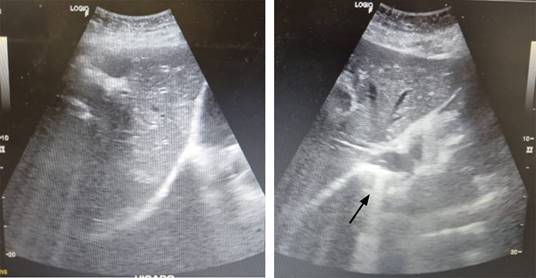

Se trata de paciente femenino de 59 años, que cuenta con antecedente de diabetes mellitus tipo 2 de larga evolución. Acude al servicio de urgencias por presentar dolor de tipo cólico en hipocondrio derecho de seis meses de evolución, de intensidad 6/10 en la escala análoga visual, sin irradiaciones, asociado a la ingesta de alimentos colecistoquinéticos, sin atenuantes, niega fiebre, ictericia, coluria o acolia. A la exploración física, con dolor a la palpación profunda en hipocondrio derecho, Murphy ausente, sin datos de irritación peritoneal. Cuenta con los siguientes laboratorios: hemoglobina 12.9 g/dl, hematocrito 37%, leucocitos 9.4 × 103/μl, plaquetas 360 × 103/μl, glucosa 178 mg/dl, creatinina 0.7 mg/dl, sodio 145 mEq/l, potasio 3.7 mEq/l, cloro 105 mEq/l, bilirrubina total 0.7 mg/dl, fosfatasa alcalina 55 U/l. Se realiza ultrasonido de hígado y vías biliares, el cual revela vesícula biliar con aumento de su ecogenicidad en toda su extensión, provocando fenómeno Wall-Echo-Shadow (WES) con dimensiones de 52.7 × 29.4 × 18.7 mm. Con pared no valorable, colédoco de 5.8 mm, sin evidencia de litos en su interior (Figura 1). Se realiza rastreo tomográfico donde se observa vesícula con volumen de 13.2 cm3, heterogénea, con presencia de densidad aire, pared engrosada de manera regular con presencia de calcificaciones, estómago distendido, con presencia de imagen hiperdensa en su interior (probable lito) (Figura 2).

Figura 2: Tomografía axial computarizada simple de abdomen, con evidencia de pneumobilia (flecha azul), imagen sugestiva de lito (flecha blanca).